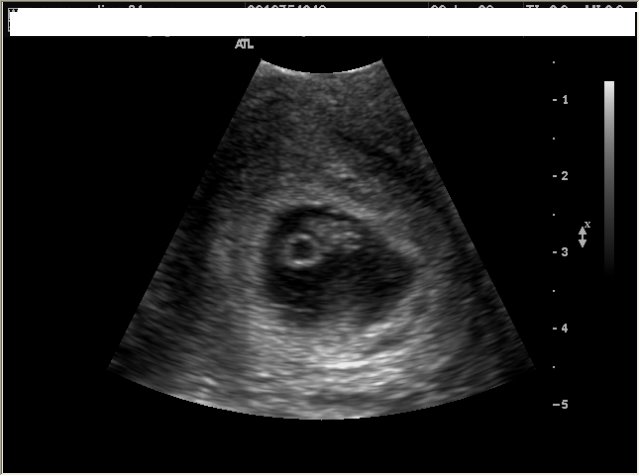

Holy hell, 8 weeks. Who would've thunk it?

I learned that this week, baby has graduated from blueberry-sized to raspberry-sized.

A close-up view of my little embryo (say cheese!) would reveal a more baby-like appearance (and thankfully, a less reptilian one). I'd see an upper lip forming, the protruding tip of that cute button nose, and tiny (and very thin) eyelids. And check out those hands and feet! My baby's webbed fingers and toes are differentiating now.